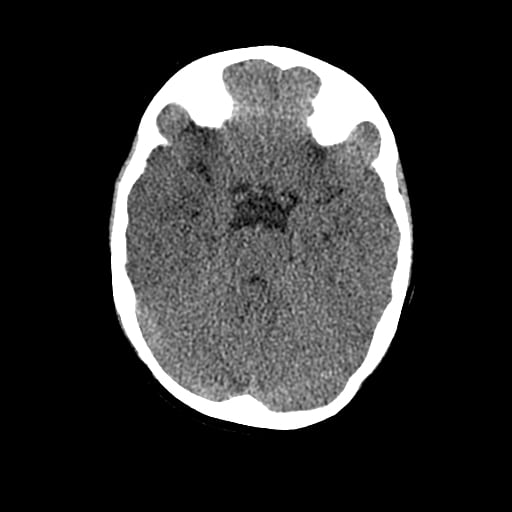

Age: 1

Sex: Male

Indication: Fall